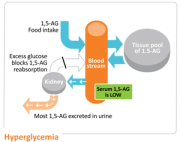

| 18:30, 12 באוקטובר 2017 | GlycoMark3.jpg (קובץ) |  |

17 קילו־בייטים | Motyk | 1 | |

| 18:28, 12 באוקטובר 2017 | GlycoMark2.png (קובץ) |  |

31 קילו־בייטים | Motyk | 1 | |

| 18:27, 12 באוקטובר 2017 | GlycoMark1.png (קובץ) |  |

29 קילו־בייטים | Motyk | 1 | |

| 18:25, 12 באוקטובר 2017 | GlycoMark.png (קובץ) |  |

12 קילו־בייטים | Motyk | 1 | |